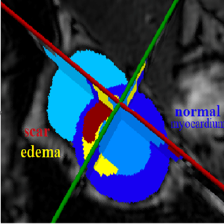

1. 数据集

来自ISICDM 2019 临床数据分析挑战赛的基于磁共振成像的膀胱内外壁分割与肿瘤检测数据集。

灰度值:灰色128为膀胱内外壁,白色255为肿瘤。

任务是要同时分割出膀胱内外壁和肿瘤部分,加上背景,最后构成一个三分类问题。